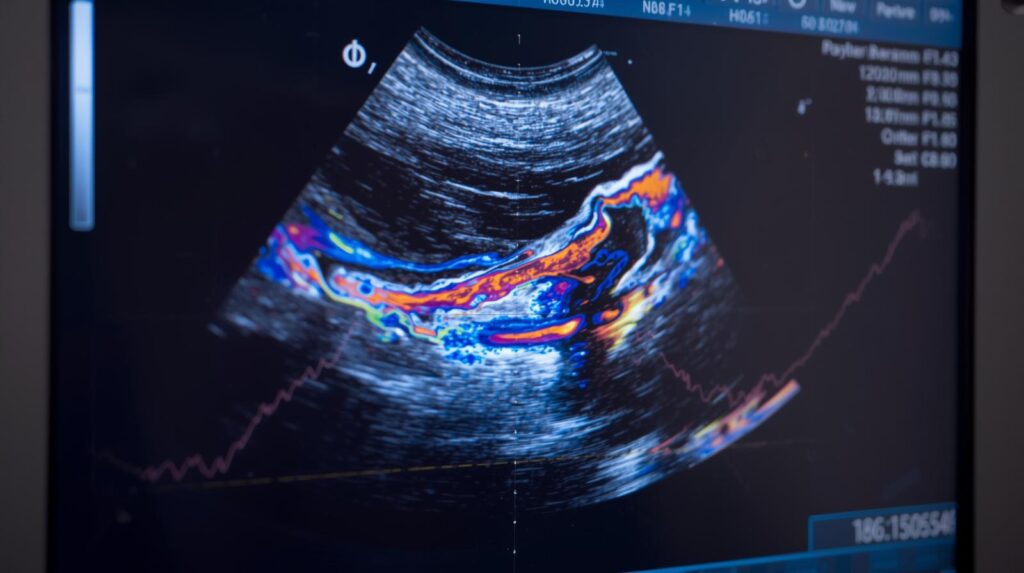

الفرق بين اشعة الحوض والسونار على الحوض السونار المنزلي

الفرق بين اشعة الحوض والسونار على الحوض

الفرق بين اشعة الحوض والسونار على الحوض عند الشعور بألم في منطقة الحوض أو الاشتباه في وجود مشكلة طبية، غالبًا... اقرأ المزيد